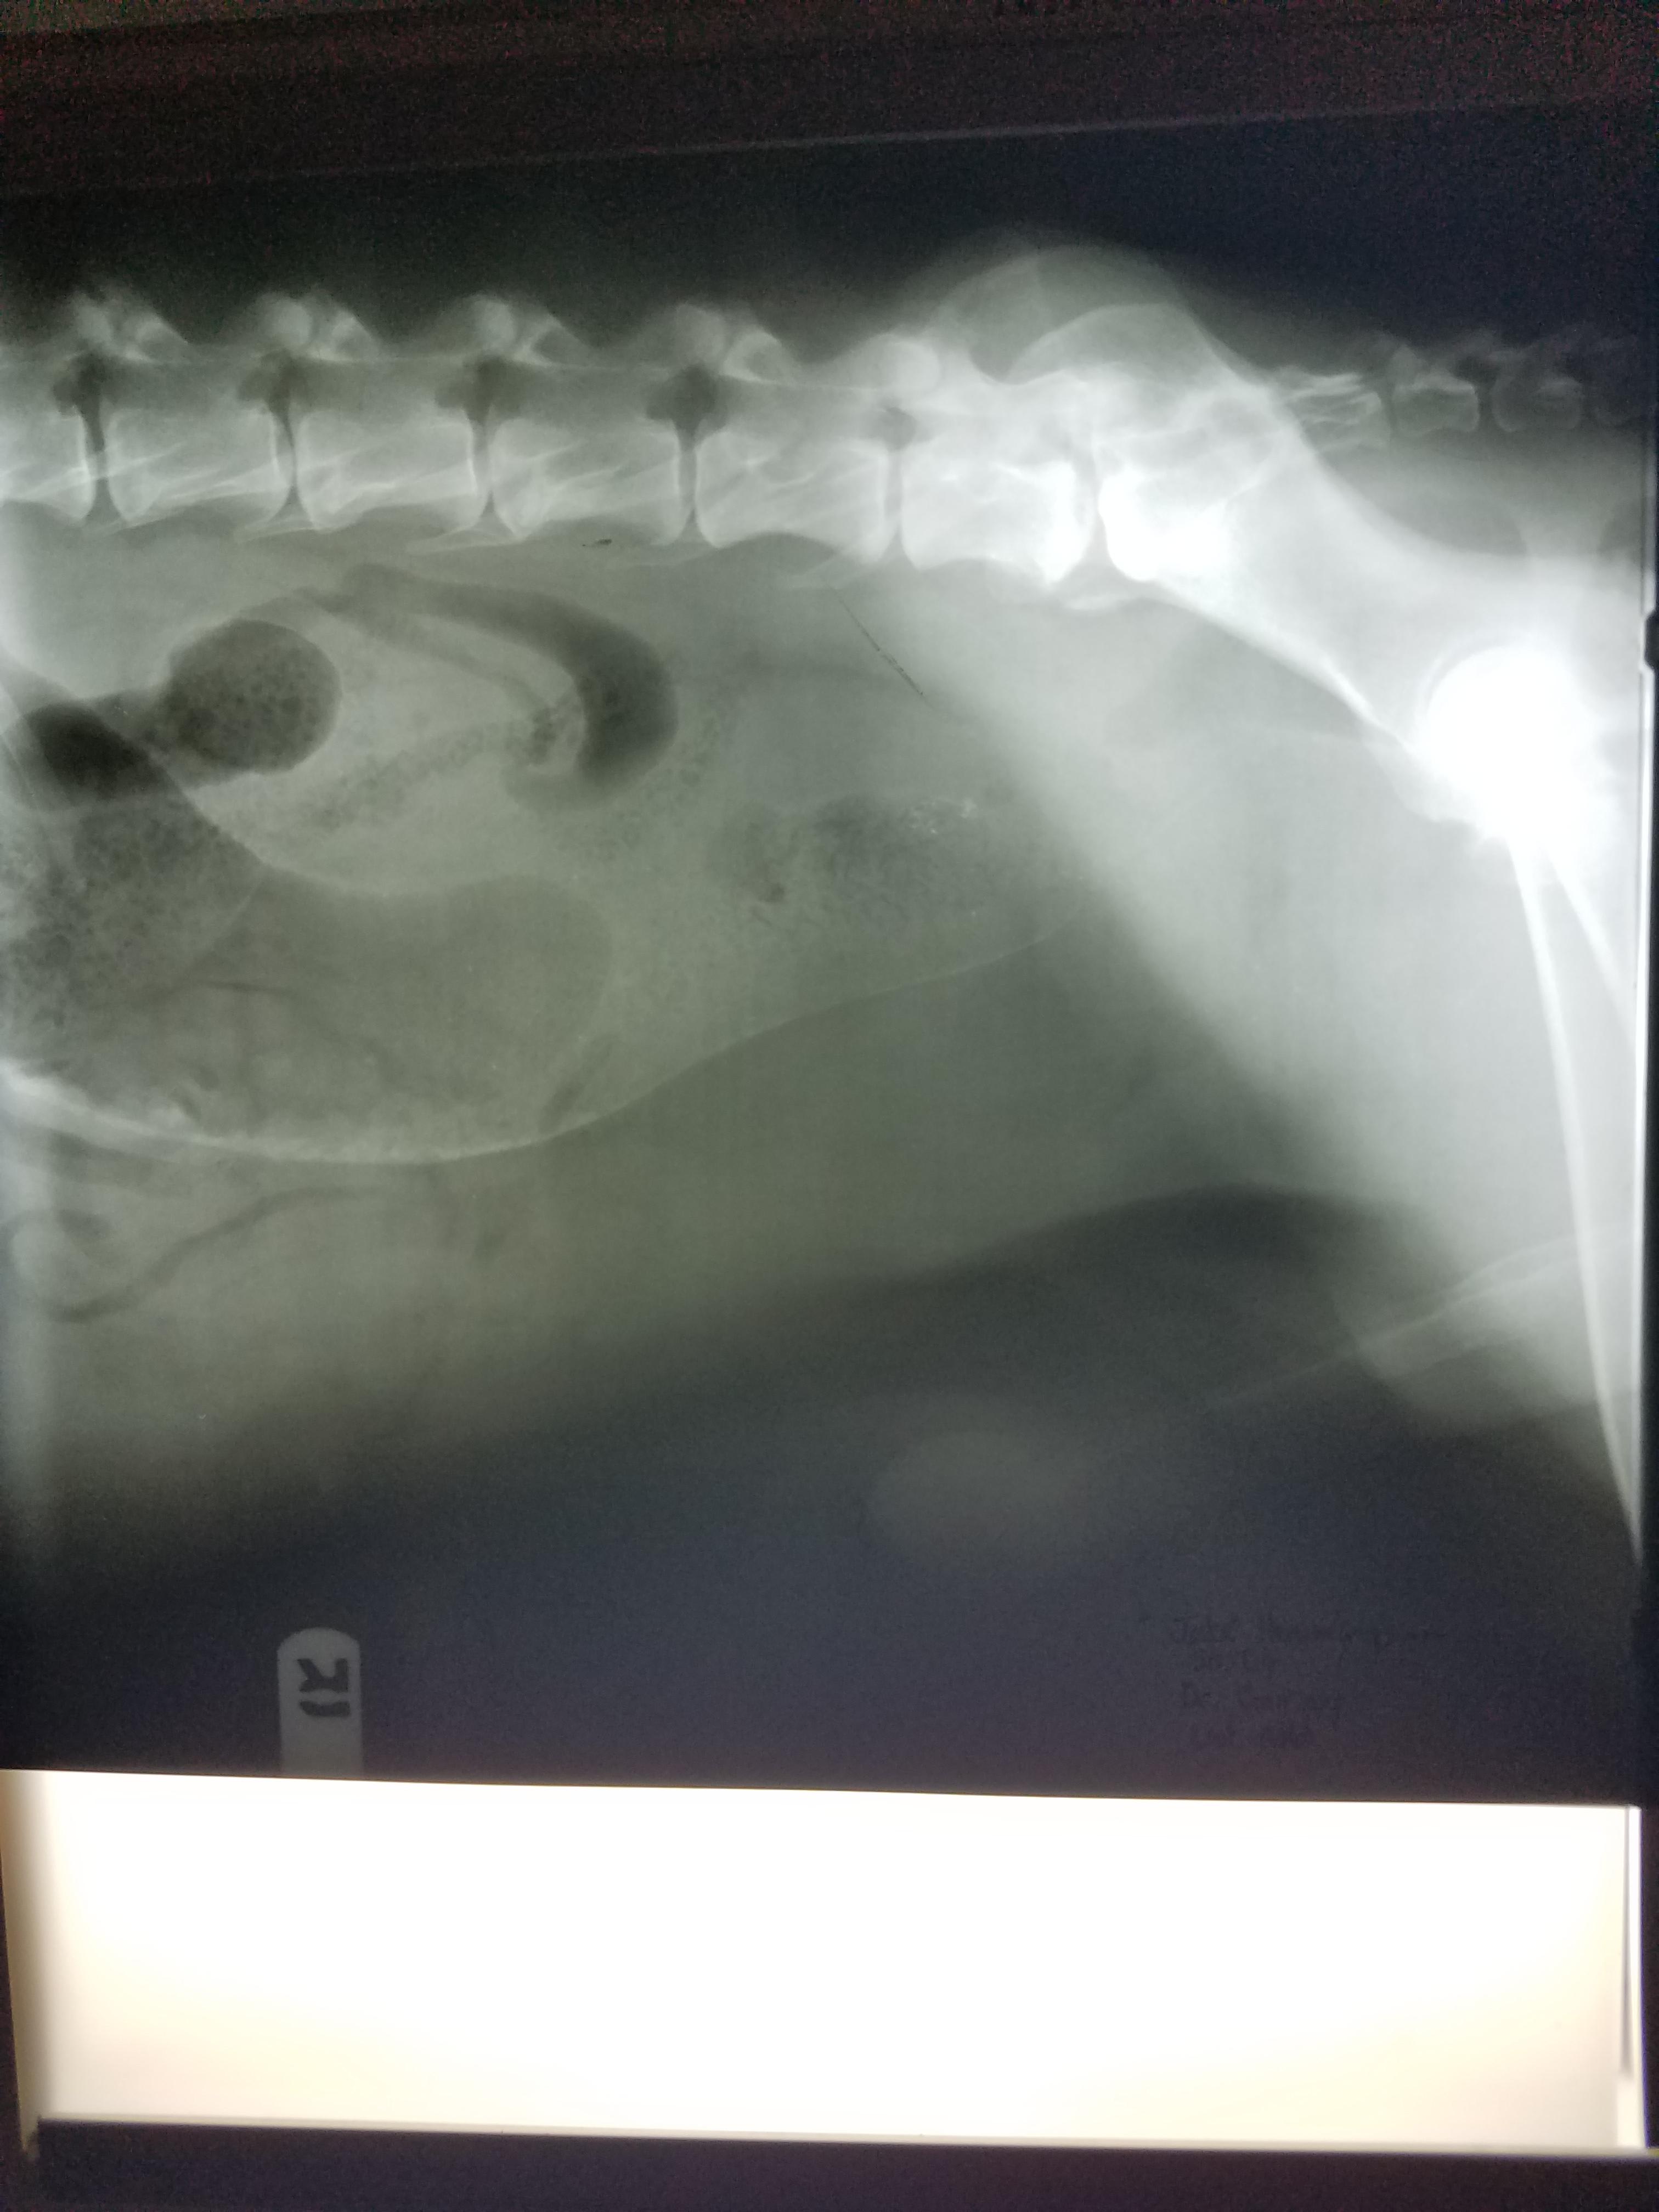

Pet's info: Dog | German Shepherd | Male | unneutered | 3 years old | 119 lbs

This an x-ray focused on the caudal abdomen. As far as I can see there is moderate distension of the last part of the intestine (colon) which is filled with feces and gas. There are no other abnormalities and the radiopacity on the ventro-dorsal view is due to an artifact rather than an actual abnormality.